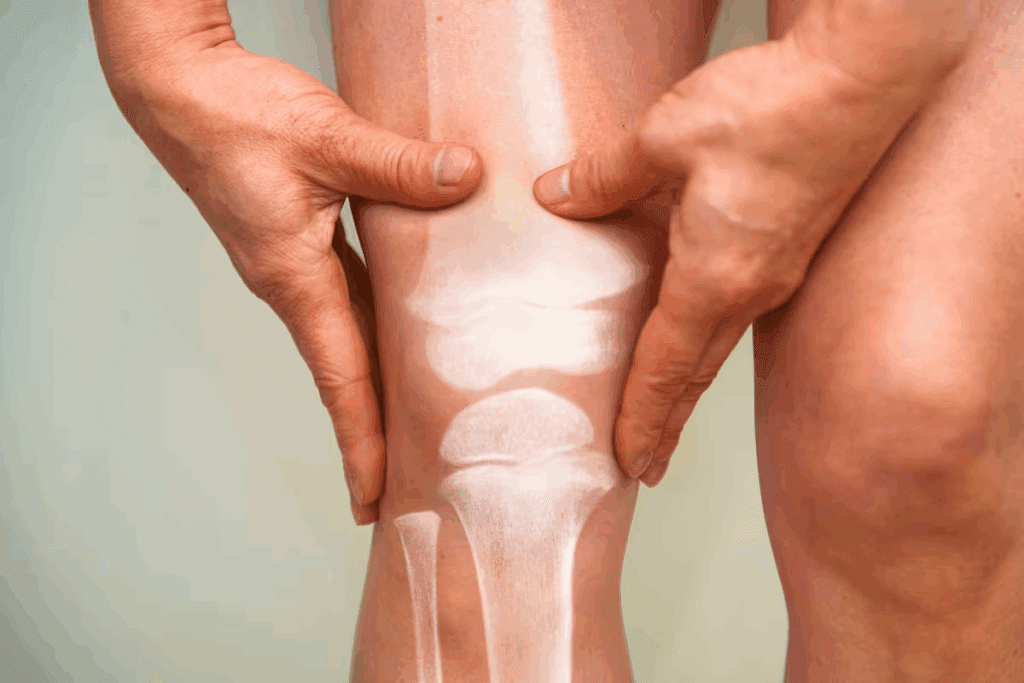

Knee Bone Dislocations

Knee bone dislocations are a big problem in orthopedics. They need quick and good treatment to fix the knee and stop pain. We’ll look at the types, causes, symptoms, and how to treat them.

Patella (Kneecap) Dislocations

The kneecap can move out of place, often from a hit or twist. Patellar dislocations happen more in people with certain knee shapes. Treatment includes fixing the kneecap and exercises to make the muscles stronger.

Tibiofemoral Joint Dislocations

Tibiofemoral joint dislocations happen when the tibia moves out of place. These are very painful and can come from big injuries. Quick doctor visits are key to check for nerve or blood vessel damage.

Treatment for knee bone dislocations depends on the problem. It can be simple care like rest and therapy or surgery for serious cases. The main goal is to fix the knee, ease pain, and avoid more problems.